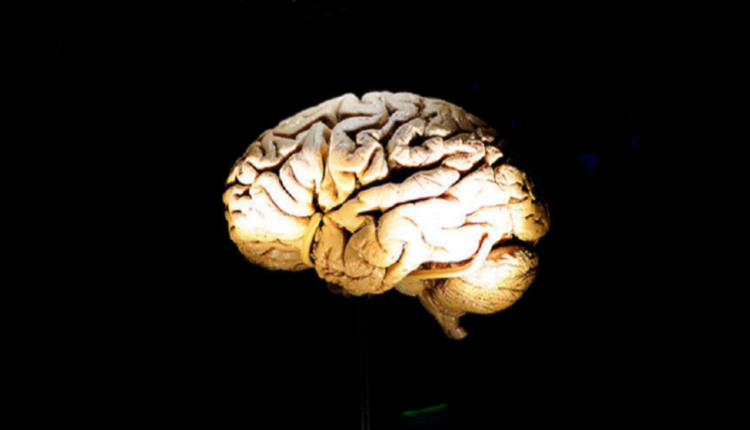

أدمغة الثدييات تبدأ في أكل نفسها عند الحرمان من النوم

تتجاوز الحاجة إلى النوم مجرد تجديد مستويات الطاقة لدينا كل 12 ساعة. وتتغير أدمغتنا في الواقع عندما ننام لإزالة المنتجات الثانوية السامة للنشاط العصبي الذي خلفه طيلة النهار.

ومن الغريب أن الأبحاث التي أُجريت على الفئران كشفت أن نفس العملية تبدأ في الحدوث في الأدمغة التي تعاني من الحرمان المزمن من النوم أيضا، باستثناء أنها بدأت في زيادة السرعة.

ووجد الباحثون أن قلة النوم المستمرة تجعل الدماغ ينظف قدرا كبيرا من الخلايا العصبية والوصلات المشبكية، وقد لا تتمكن استعادة النوم من عكس الضرر.